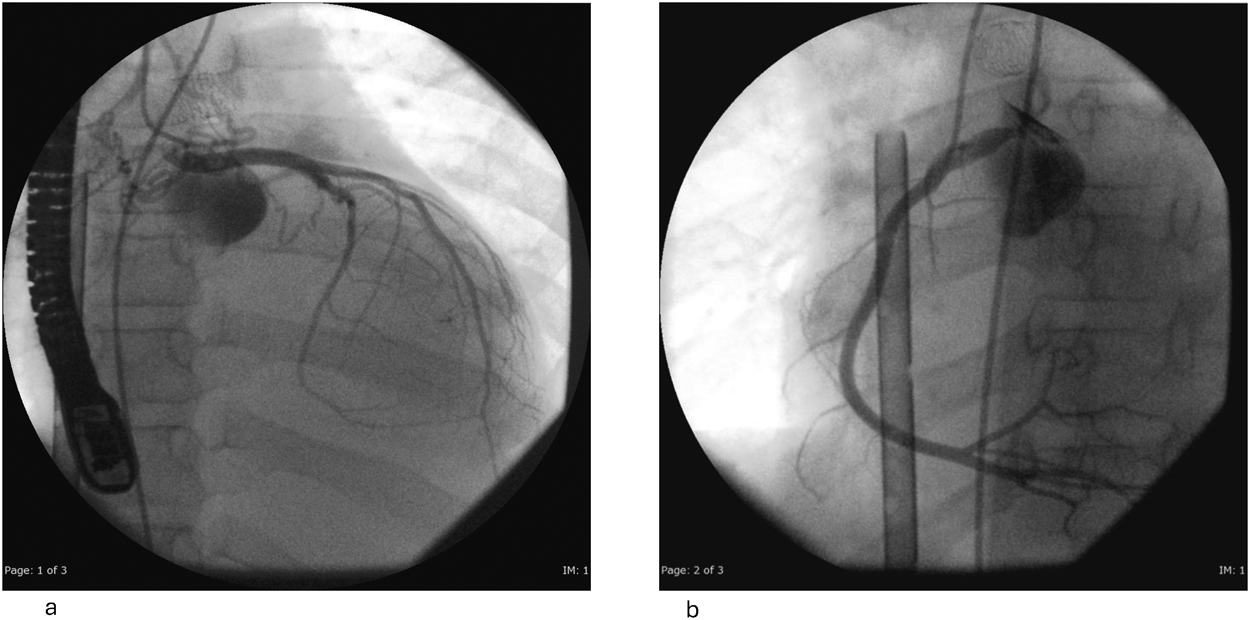

Impella®循環補助用心内留置型ポンプカテーテル(Impella® CP)と静動脈型体外式膜型人工肺により劇症型心筋炎の左室unloadingが著効した12歳男子例—体格の小さい患者における管理上の注意点A 12-year-old male case of successful left ventricular unloading utilizing Impella CP® and veno-arterial extracorporeal membrane oxygenation due to fulminant myocarditis—Precautions for management in patients with small stature